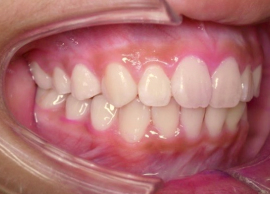

側面

- After